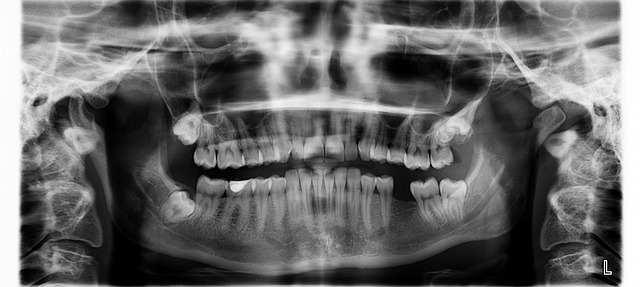

부정교합은 치아의 이상적인 교합 상태가 아닌 상태를 의미합니다. 일반적으로 상·하악 치아들이 정확하게 맞물리지 않거나 교합이 부적절한 경우를 말합니다. 부정교합은 다양한 원인에 의해 발생할 수 있으며, 개인의 구강 구조, 치아의 크기와 위치, 교합근, 턱관절 등이 관련되어 있습니다.

부정교합의 치료는 개인의 상황과 부정교합의 원인에 따라 다양하게 접근될 수 있습니다. 교정치과의사와의 상담을 통해 교정치료를 선택할 수 있습니다. 교정치료는 치아와 턱의 위치와 교합을 개선하기 위해 다양한 치과 교정기를 사용하는 것을 의미합니다. 그러나 심미적으로만 접근한 교정치료는 턱관절과 경추의 문제로 연결될 수 있으니 전신을 바로잡을 수 있도록 할 수 있는 전문 의사를 잘 찾아야 합니다. 구강 보건 전문가는 올바른 구강 관리 기술과 입안 자세를 가르쳐 줄 수 있습니다. 개인에게 맞는 칫솔, 치실 사용법과 구강 청결 유지에 대한 교육을 받는 것이 중요합니다. 부정교합이 턱 관절 문제와 관련이 있는 경우, 턱관절 치료를 통해 부정교합을 개선할 수 있습니다. 이를 위해 턱관절 재교육, 마사지, 물리치료 등의 치료 방법을 사용할 수 있습니다. 부정교합은 각 개인의 상황에 따라 다양한 원인이 있을 수 있으므로, 개인 맞춤형 치료 계획이 필요합니다. 의사와 상담하여 정확한 진단과 개인에게 적합한 치료 방법을 결정하는 것이 중요합니다. 부정교합의 치료는 전문적인 도움과 지속적인 관리가 필요할 수 있습니다.